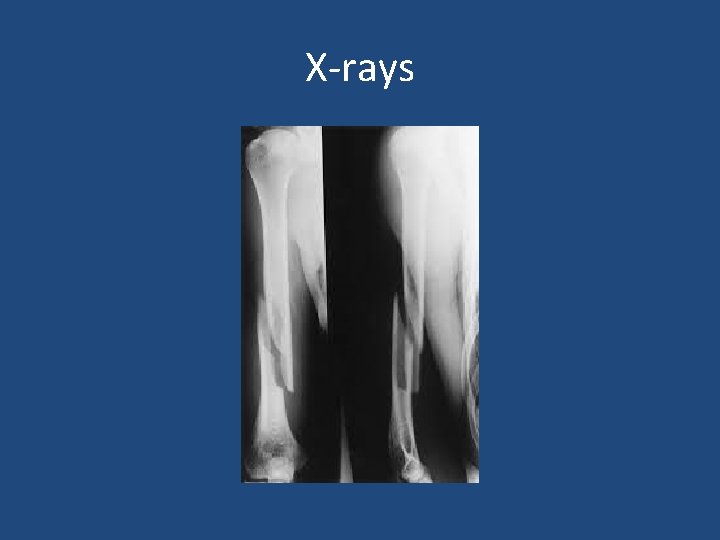

X-rays